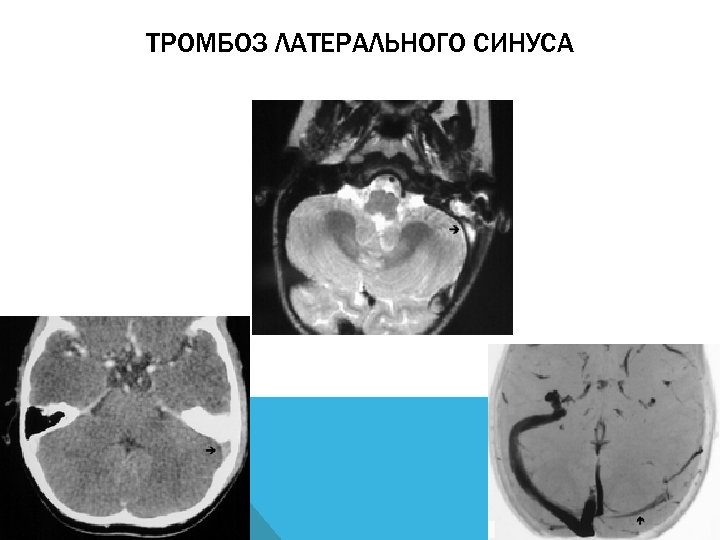

ЦЕРЕБРАЛЬНЫЙ ВЕНОЗНЫЙ ТРОМБОЗ СИНУС-ТРОМБОЗ И ТРОМБОЗ ВЕН

СИНУС-ТРОМБОЗ Наиболее частая локализация: 1. Верхний сагиттальный синус 2. Латеральный (сигмовидный и поперечный) синус

ТРОМБОЗ ЛАТЕРАЛЬНОГО СИНУСА